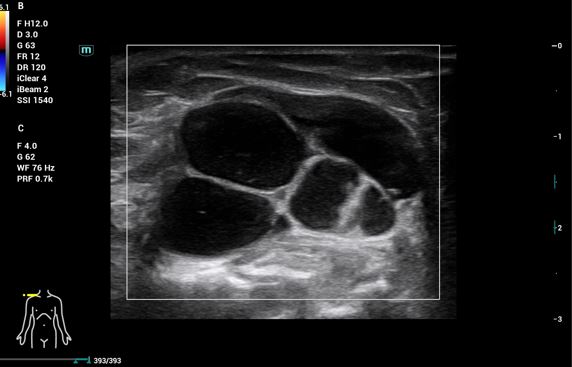

Se realiza ecografía hombro derecho para ayudarnos con el diagnóstico diferencial: tumores sólidos, quistes o gangliones de contenido líquido.

Ecografía de hombro derecho: Lesión multilobulada anecoica, sin claro refuerzo posterior, bien delimitada con paredes gruesas. Doppler negativo.

RMN: Cambios hipertróficos en la articulación acromio-clavicular con líquido e imagen de ganglión de unos 5 cm. Desgarro del manguito de los rotadores con desgarro completo del tendón supraespinoso. Desgarro del tendón infraespinoso, del tendón subescapular, del redondo menor y del tendón de la cabeza larga del bíceps braquial. Líquido en la bolsa subacromiosubdeltoidea y subcoracoidea.